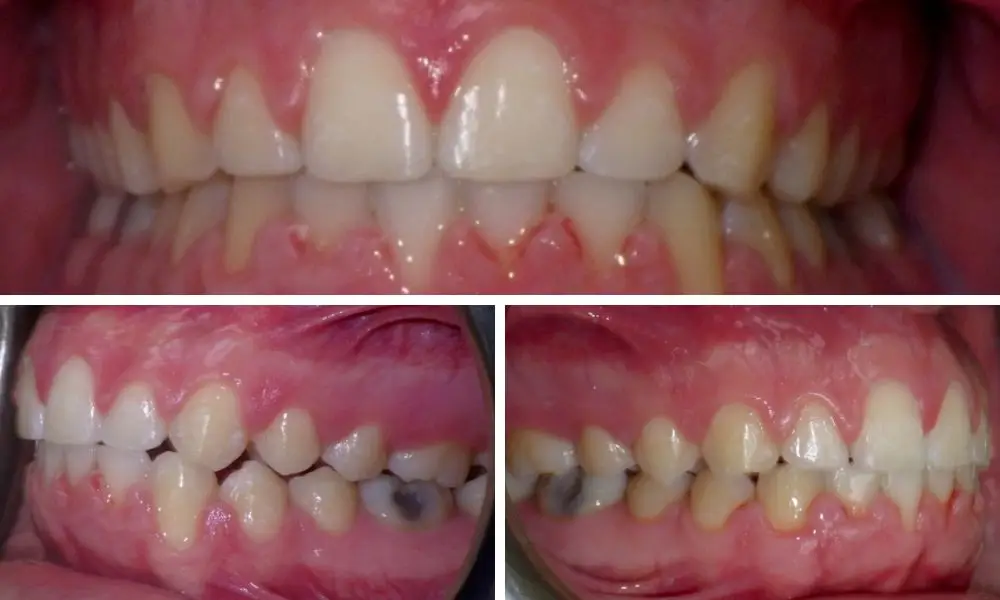

Invisalign aligners are an effective tool for correcting dental crowding. Tooth crowding is when teeth overlap or twist because there's not enough space in the jaw. If you have this problem, a doctor will check if Invisalign is right for you. Sometimes, extra steps are needed for severe crowding.

Invisalign fixes this orthodontic issue by straightening your teeth and then spreading them out. You need to wear the aligners for about 22 hours a day.

In some cases, doctors do a simple procedure called IPR. This means removing a tiny bit of enamel from your teeth to make more room. Invisalign can also help with other issues, like treating crossbite and underbite..